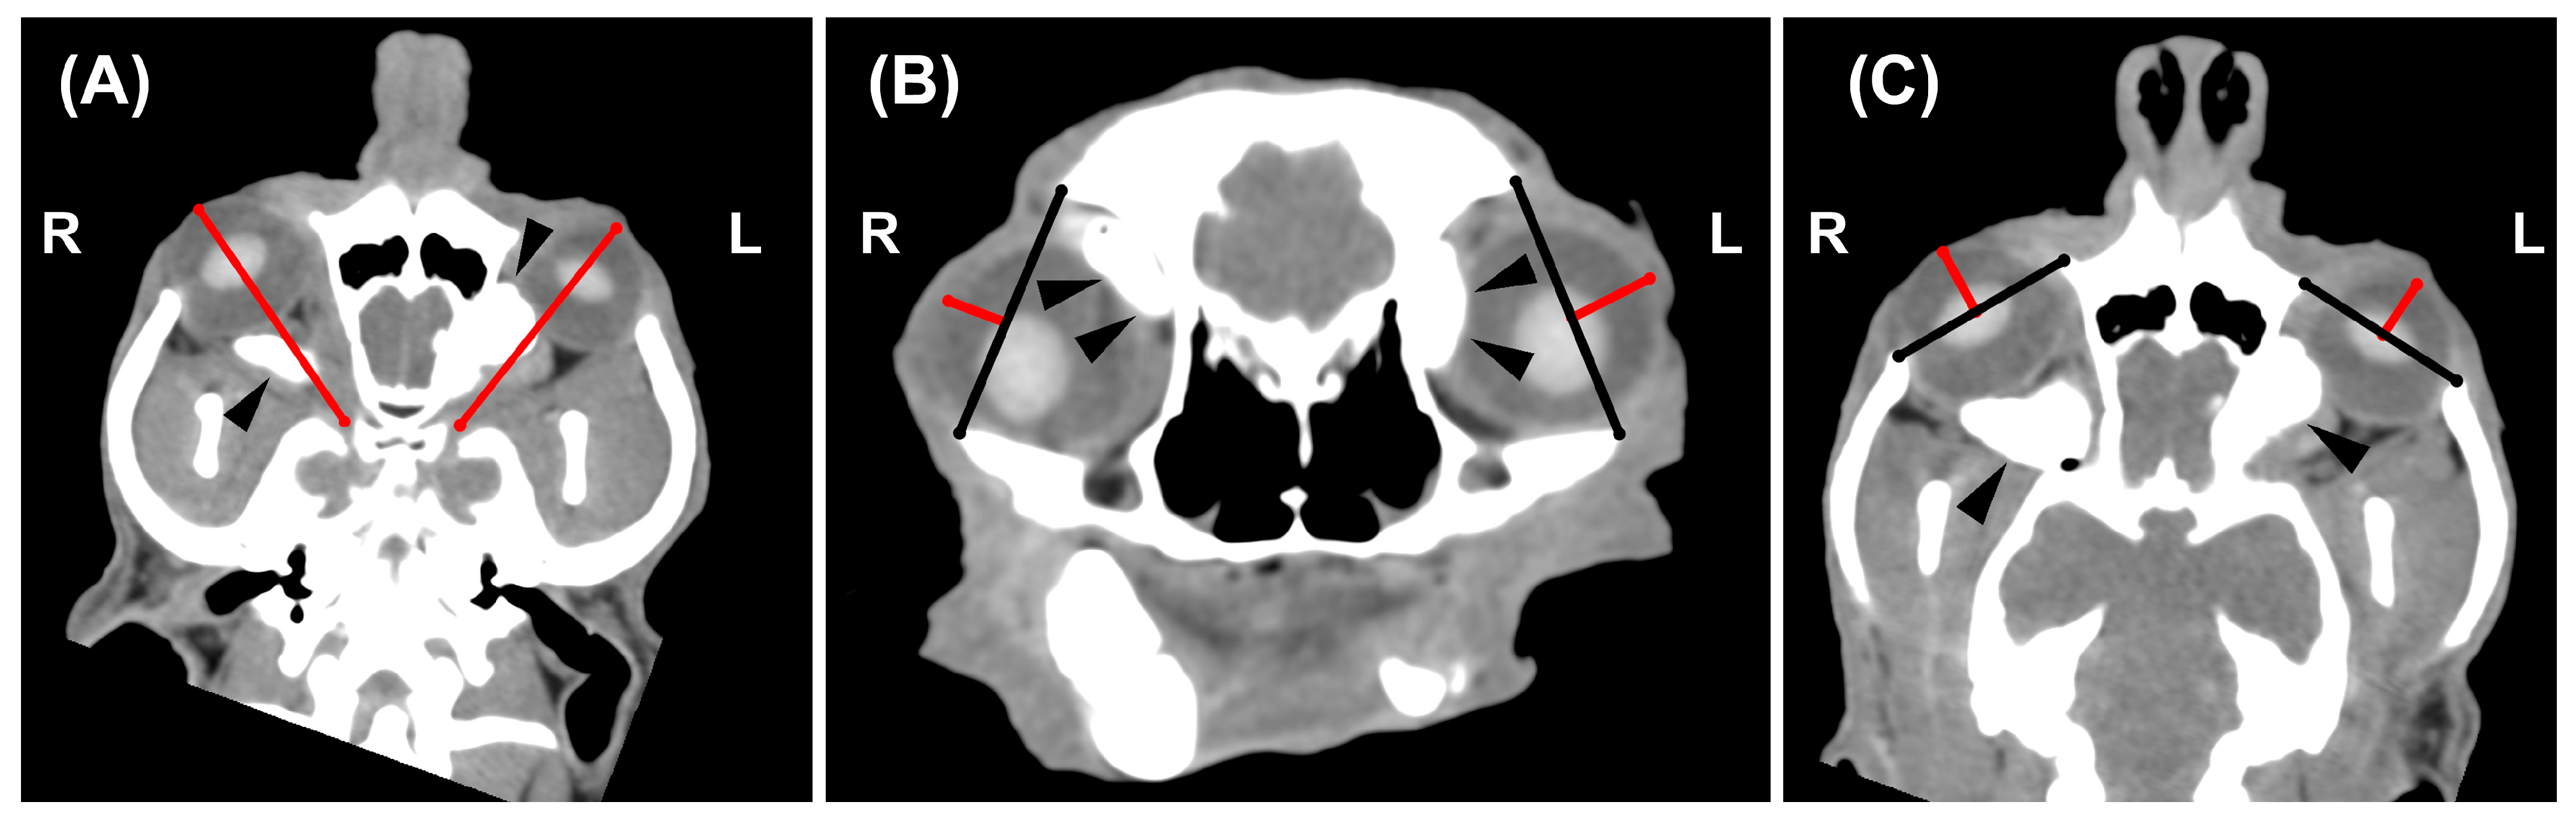

3.4. CT Images Findings

3.5. Statistical Results